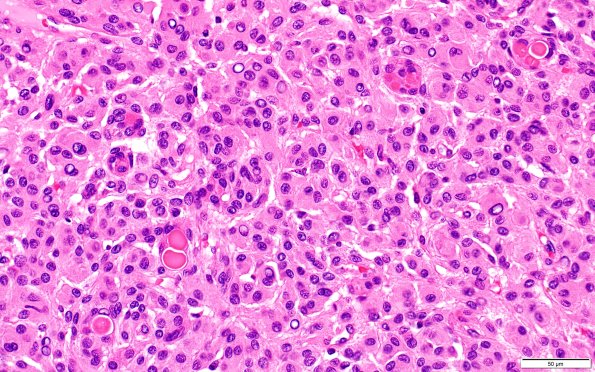

17B1,2 H&E-stained sections show a dural-based meningioma, arranged largely in a whorled pattern with numerous mini-whorls. Numerous secretory ("pseudopsammoma") bodies are seen in this routine H&E (17B1) and stain with polyclonal CEA (17B2) stains. The tumor cells have a moderate amount of cytoplasm, indistinct cytoplasmic borders, and predominantly round to oval nuclei with frequent nuclear grooves or clearing and rare intranuclear cytoplasmic pseudoinclusions. Atypical features (necrosis, hypercellularity, sheeting, prominent nucleoli, and/or small cell change) are not identified. The tumor demonstrates dural invasion, including through its entire thickness focally. Mitoses are difficult to find. (H&E)